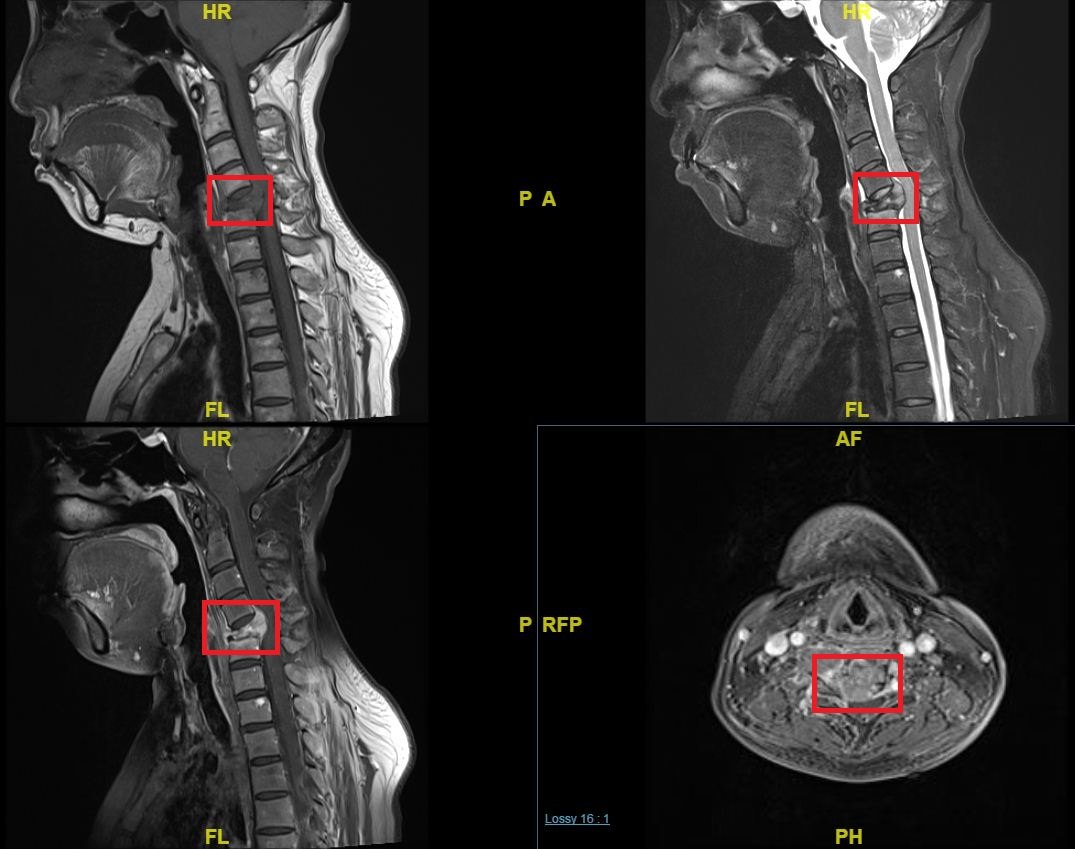

脊柱肿瘤科普

脊膜瘤(meningioma)是椎管内常见的肿瘤之一